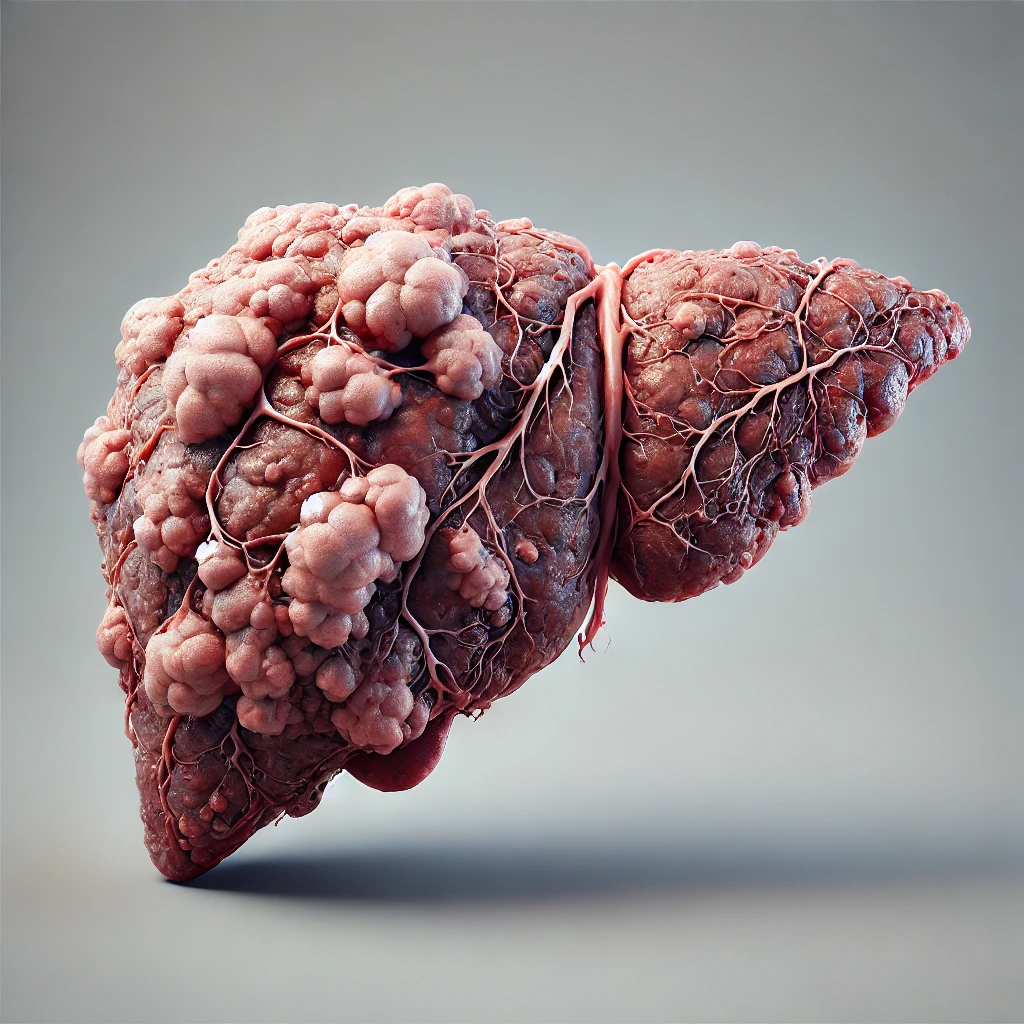

Ele é capaz de tratar completamente as principais doenças que podem atingir seu fígado, a (DHGA) Doença Hepática Gordurosa Alcóolica, (DHNGA) Doença Hepática Gordurosa não Alcóolica.

É um desequilíbrio metabólico que afeta sua saúde física e sua qualidade de vida.

Ajuda a restaurar a função hepática, recuperar níveis de energia da juventude e derreter anos de gordura abdominal!

Figdetox age restaurando as celulas do Fígado, fazendo com que seu figado volte a funcionar normal, eliminando a gordura e se auto regenerando.